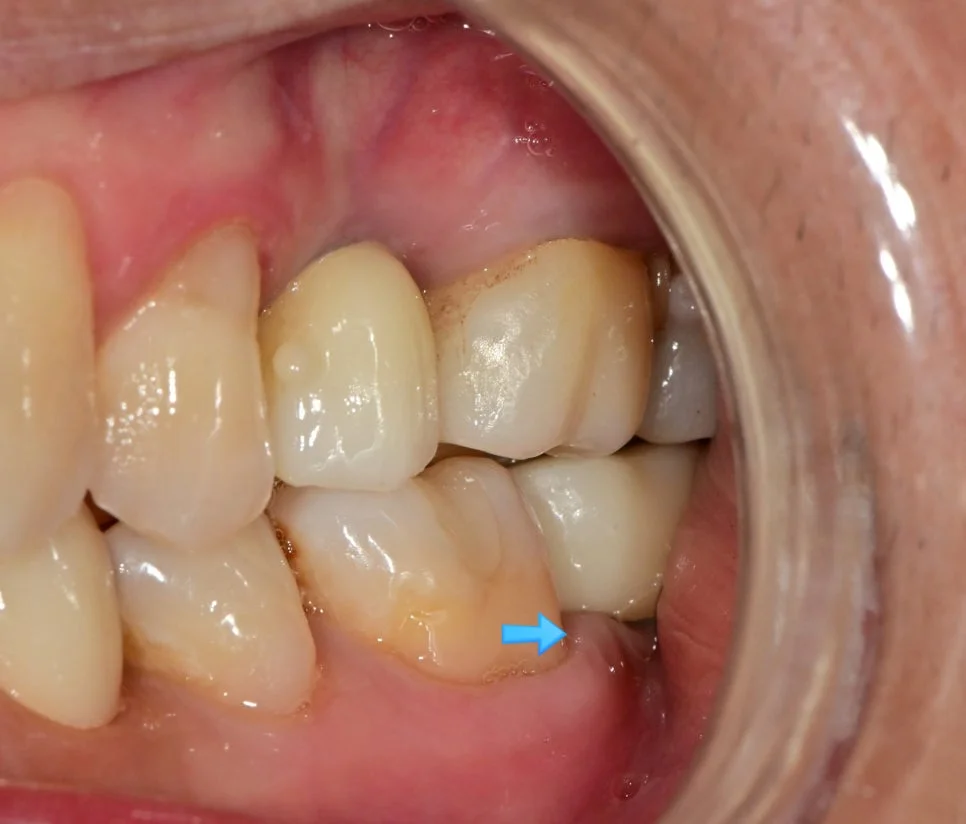

사례 1: 임플란트 보철 재제작으로 음식물 끼임 해결

왼쪽 아래 잇몸의 통증을 호소하신 환자분입니다.

사진을 보면 음식물이 고여 있고 주변 잇몸은 많이 부어있는 양상인데요. 임플란트와 그 바로 앞 치아 사이가 문제입니다.

사진을 찍어보면 명확하게 임플란트와 치아 사이에 틈이 보이는데요. 이 정도 공간이면 음식물이 정말 엄청나게 끼게 됩니다ㅜ

음식물이 끼는 사이 틈에는 충치/잇몸질환이 둘 다 잘 생기게 되므로 음식물 끼임은 그 자체로 문제입니다ㅜ